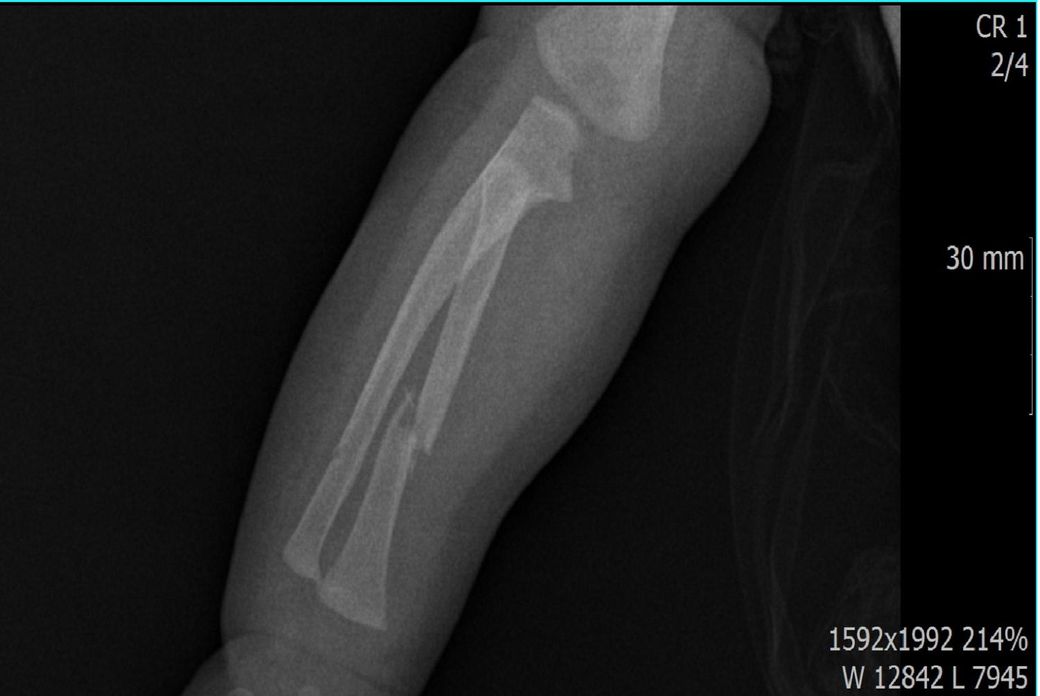

다름이 아니라, 첨부드린 엑스레이(X-ray) 사진처럼 골절 사실을 알게 되고 골절 발생 시점 대략적으로나마 추정시기를 파악하려고 문의 드리게 되었습니다

1) 3월 30일 촬영한 X-ray만으로 정확한 골절 시기를 100% 특정하는 데에는 한계가 있다는 점 충분히 인지하고 있기에 촬영날짜 기준으로 대략적으로 어느정도 시점에서 발생되었을 것으로 추측(ex 당일, 7~10일전, 7~14일 전, 10일 ~ 20일전, 14일 ~ 30일전 등등등)되는지 이해하고 싶습니다.

• 4번 째 사진

엑스레이 만으로 골절 발생 시기를 정확히 특정하긴 어렵지만 뼈의 염증 반응, 골막 반응, 골흡수 신생 정도를 통해 대략 추정은 가능합니다. 보통 급성 골절은 1~7일 이내, 골절선이 희미해지고 골막 반응이 보이면 10~20일 전후 뼈 융합이 일부 보이면 3~4주 이상 경과로 추정할 수 있습니다. 3월 30일 촬영 기준, 골절선의 형태와 신생골 유무에 따라 7~21일 내외의 외상으로 판단되는 경우가 많아요!

골절의 정확한 시기를 예측하기는 어려움이 있으나, 뼈의 골절선이 뚜렷하게 관찰된다면 0~7일 이내의 가능성이 있고 흐린 가골이 관찰되거나 골막의 일부 반응이 관찰된다면 7~14일 이내, 가골이 형성중인것이 관찰된다면 2-3주 이상의 골절시기를 대략적으로 유추해볼 수 있습니다.

골절의 상태를 보고 골절선이 선명하고 부위에 가골이 형성되지않았다면 보통 일주일 이내, 골절선이 보이지만 주변 부위에 가골이 조금씩 있다면 2주 이내, 골절선이 잘안보이고 가골이 보인다면 한달 이내로 판단 할 수 있습니다.

지금과 같이 엑스레이상 골절이 잘 보이는것으로 보아 2주 이내에 특별한 이슈가 있을만한지 생각해보시길 바랍니다^^